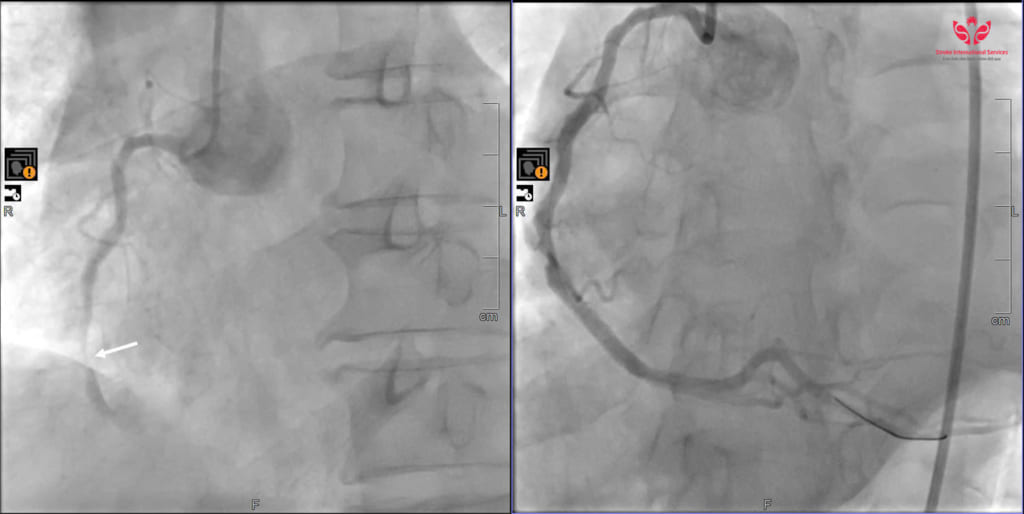

Tại Bệnh viện Đa khoa Quốc tế S.I.S Cần Thơ, ông L. được chẩn đoán nhồi máu cơ tim cấp ST chênh lên giờ thứ 3, ngưng tim với hồi sức thành công. Ngay lập tức, các bác sĩ chuyển ông đến Đơn vị can thiệp DSA để tiến hành chụp và nong mạch vành bị tắc nghẽn.

Kết quả chụp DSA cho thấy, nhánh động mạch vành phải của ông bị tắc hoàn toàn, trong khi nhánh liên thất trước của động mạch vành trái hẹp đến 90%.

Sau gần 50 phút, ekip can thiệp đã thành công đặt 1 stent vào nhánh động mạch vành phải, giúp tái thông dòng chảy máu cho tim. Sau can thiệp, bệnh nhân hồi phục kỳ diệu. Chỉ ba giờ sau, dù vẫn thở máy, ông L. đã tỉnh táo, nghe hiểu và không có dấu hiệu tổn thương thần kinh.